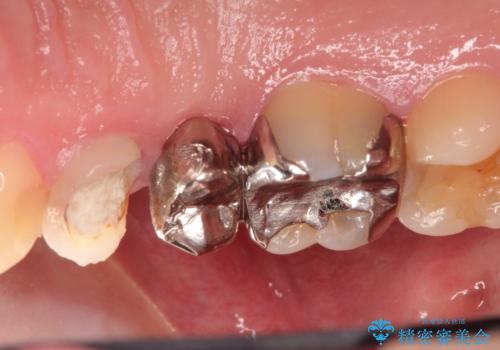

右上のブリッジが途中で切断されて、手前の歯が根の治療の途中でした。

以前は保険治療で作られた金属のブリッジを装着されていましたが、オールセラミックブリッジを装着することにより、審美的にも改善されました。